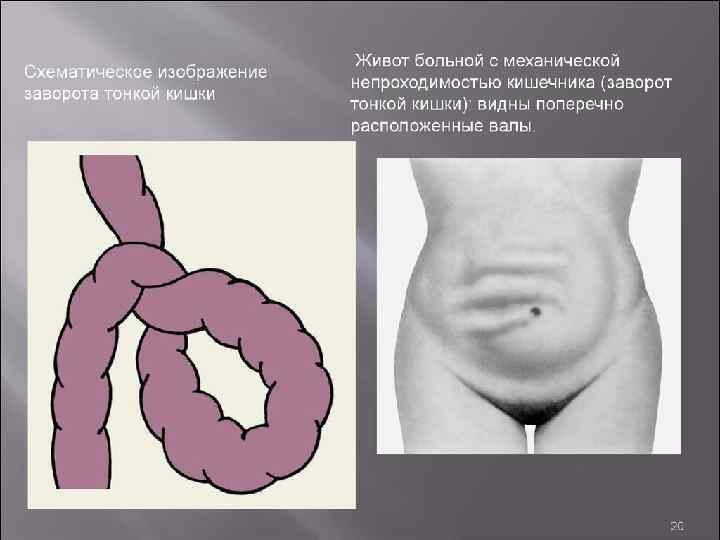

Механическая и динамическая непроходимость кишечника Анамнез Ведущими симптомами острой кишечной непроходимости являются боли в животе, его вздутие, рвота, задержка стула и газов. Они имеют различную степень выраженности в зависимости от вида непроходимости, уровня и длительности заболевания. Боли обычно возникают внезапно, вне зависимости от приема пищи, в любое время суток, без каких либо предвестников. Им свойственен схваткообразный характер, связанный с периодами гиперперистальтики кишечника, без четкой локализации в каком либо отделе брюшной полости. При обтурационной кишечной непроходимости вне схваткообразного приступа они обычно полностью исчезают. Странгуляционной непроходимости свойственны постоянные резкие боли, периодически усиливающиеся. При прогрессировании заболевания острые боли, как правило, стихают на 2 3 и сутки, когда перистальтическая активность кишечника прекращается, что служит плохим прогностическим признаком.

Клиническая картина Основные симптомы: Боль без четкой локализации, схваткообразная или постоянная с разной степенью интенсивности. симптом Тэвенара – боль при пальпации на 2 поперечных пальца ниже пупка(проекция корня брыжейки тонкой кишки). При странгуляционной непроходимости. вздутие живота – может быть симметричным и ассиметричным(странгуляционная). Характерно для высокой непроходимости. видимая перистальтика – характерна для механической непроходимости. Рвота – многократная, ненадолго приносящая облегчение, переходящая постепенно в каловую рвоту. симптом Валя – высокий тимпанит над проекцией толстой кишки – характерно для ранней механической непроходимости. симптом Шимана – западение живота в левой подвздошной области, в то время как в правом подреберье вздутие толстого кишечника, при завороте сигмовидной кишки. симптом Склярова – шум плеска при сукуссии. симптом Спасокукоцкого Вильмса – шум падающей капли, растянутые петли кишечника. Аускультация живота, по образному выражению наших хирургических учителей, необходима для того, чтобы «услышать шум начала и тишину конца» (Г. Мондор). «гробовая тишина» отсутствие перистальтики. пальцевое ректальное исследование – «каловый завал» , вздутие ампулы. интоксикационный синдром – температура, тахикардия, головная боль и слабость – признак калового застоя.